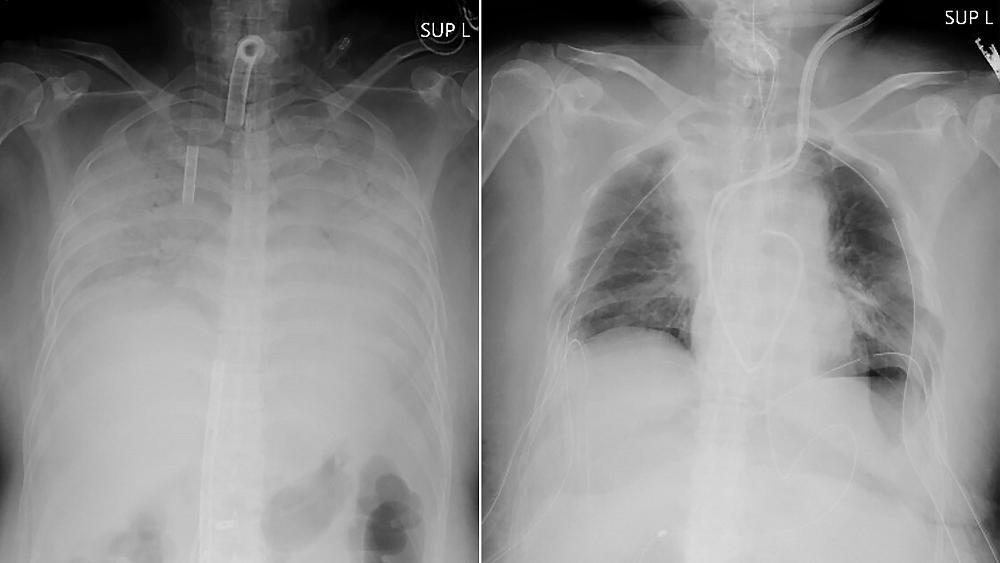

Doctors in Japan announced Thursday they have successfully performed the world’s first transplant of lung tissue from living donors to a patient with severe lung damage from COVID-19.

The recipient, identified only as a woman from Japan’s western region of Kansai, is recovering after the nearly 11-hour operation on Wednesday, Kyoto University Hospital said in a statement. It said her husband and son, who donated parts of their lungs, are also in stable condition.

The woman contracted COVID-19 late last year and developed breathing difficulties that rapidly worsened. She was placed on a life support machine that works as an artificial lung for more than three months at another hospital because her lungs were so severely damaged.

Even after she was free of the virus, her lungs were no longer functional or treatable, and the only option for her to live was to receive a lung transplant, the university said.